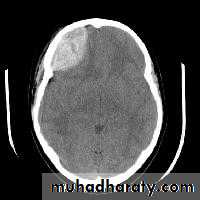

Acute SDH

CT findingCrescent shape or oval shape of hyper density area their inner medial margin is irregular shaggy

Associated with edema which cause shifting of the midline .

The source of bleeding hematoma is venous , not associated with # , but occur as a result of disruption of subdural vein , more commonly to occur in the old age group , due to brain concussion , ( brain atrophied wide SAS ) & in the pediatric age group the SAS &cistern are wide also .